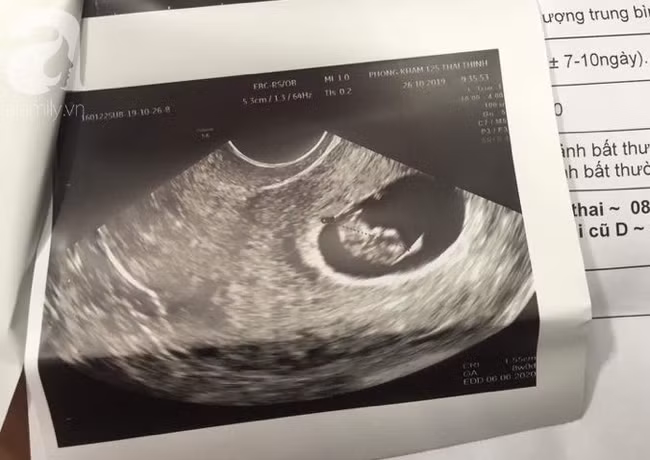

Đến ngày 29/10 vì lo sợ, chị A. được gia đình đưa đến một BV tại Hà Nội điều trị. Kết quả xét nghiệm tại đây khiến mọi người ngỡ ngàng khi nữ bệnh nhân được phát hiện đang mang thai 8 tuần. Như vậy vào thời điểm thực hiện hút mỡ bụng, cái thai trong bụng chị A. đã 4 tuần tuổi.

Kết quả chẩn đoán có thai tiếp tục được khẳng định tại BV AIH (TP.HCM).

Sau đó, gia đình tiếp tục đưa chị A. đến xét nghiệm, siêu âm tại Bệnh viện AIH (TP.HCM). Kết quả vẫn chẩn đoán người phụ nữ có thai.